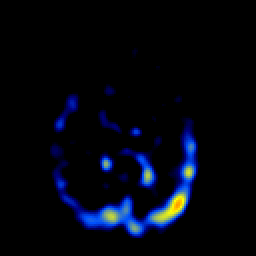

SPECT TL Study #2 -- Slice #43

[Home][Help][Clinical][Tour 1][Tour 2][Tour 3] Slice 43